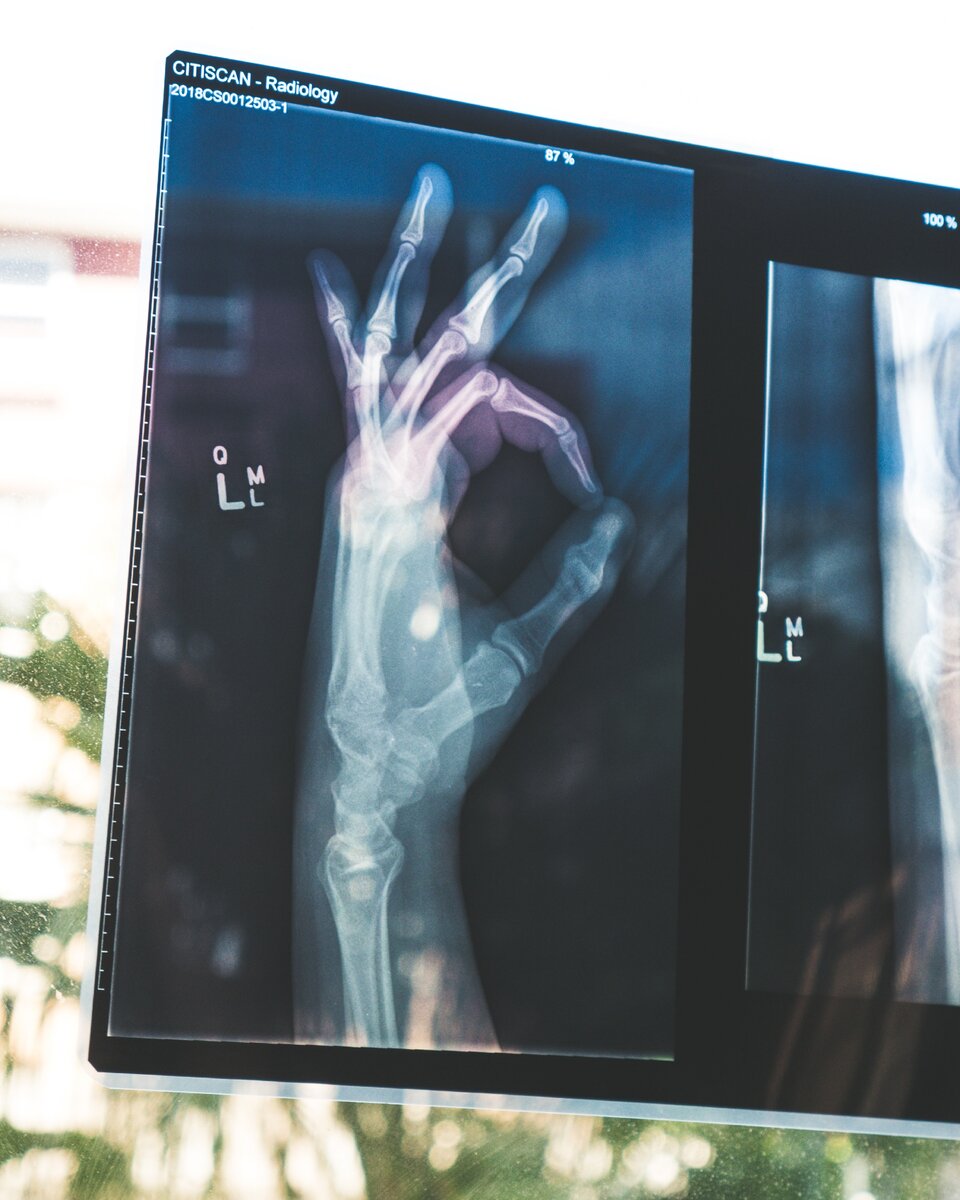

Именно так я выгляжу, когда вижу мужа за работой. (изображение из открытых источников)